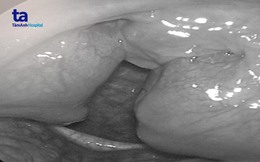

20 năm "ngáy sấm" vì khối amidan to như trứng gà

Người đàn ông trẻ bị khối amidan kích thước 4cm x 4cm bít gần hết đường thở, gây ra chứng ngưng thở khi ngủ và khiến gia đình mất ngủ do tiếng "ngáy sấm" hằng đêm.